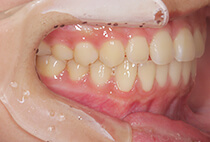

治療前

治療後

しっかり前歯を下げるために、インプラントアンカーを使用してコントロールしました。

かみ合わせが整うと咬筋の過緊張が改善。

過緊張による筋肉肥大も改善しフェイスラインもすっきりしました。